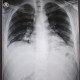

Izin bertanya dok, berapa lama flek pada paru pasien sembuh post covid akan hilang? Edukasi atau terapi apa yang bisa kita berikan pada pasien agar flek dapat berkurang? Berikut saya lampirkan foto rontgen terakhir pasien 1 hari sebelum pulang

Coba dokter lanjutkan ke ct scan toraks utk melihat GGO